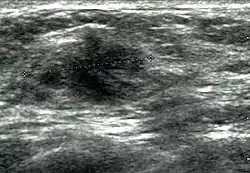

Cancer ultrasound image

Breast ultrasound is a medical imaging technique that uses medical ultrasonography to perform imaging of the breast. It can be performed for either diagnostic or screening purposes[1] and can be used with or without a mammogram.[2] In particular, breast ultrasound may be useful for younger women who have denser fibrous breast tissue that may make mammograms more challenging to interpret.[3][4]

Elastography is a type of ultrasound examination that measures tissue stiffness and can be used to detect tumours.[7] Breast ultrasound is also used to perform fine-needle aspiration biopsy and ultrasound-guided fine-needle aspiration of breast abscesses.[8]

Breast ultrasound is typically performed using a frequency of 7 to 14 Megahertz, and may also include ultrasound of the axillary tail of the breast and axillae to detect abnormal nodes in the axilla, as lymphatic drainage of parts of the breast occurs through axillary lymph nodes.